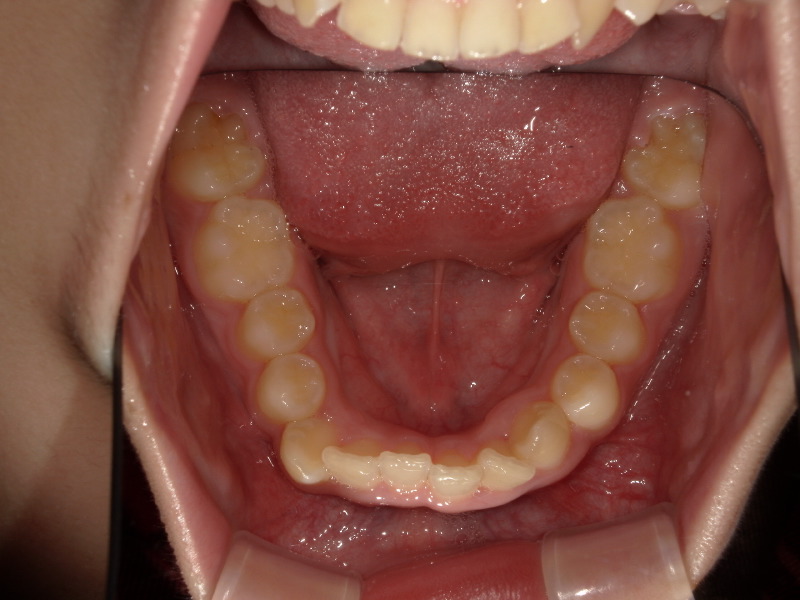

確かに上の歯は綺麗ですが、下の歯にはガタつきが残っています。

半年後の下の歯の写真です。

がたつきがあったのも綺麗になり、調和の取れた歯並びへ変わってきています!